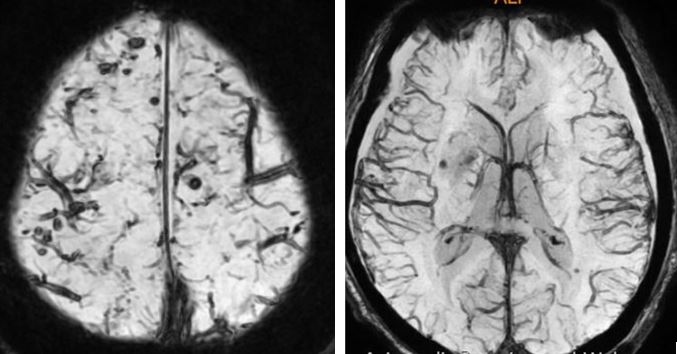

- CT brain. Comparison made with CT brain yesterday – 12 June 2024.

Impression: Right parietal extra-axil haemorrhage, stable in size compared to previous.

Bilateral fronto-temporo-parietal subdural hygroma.

No new intracranial haemorrhage.